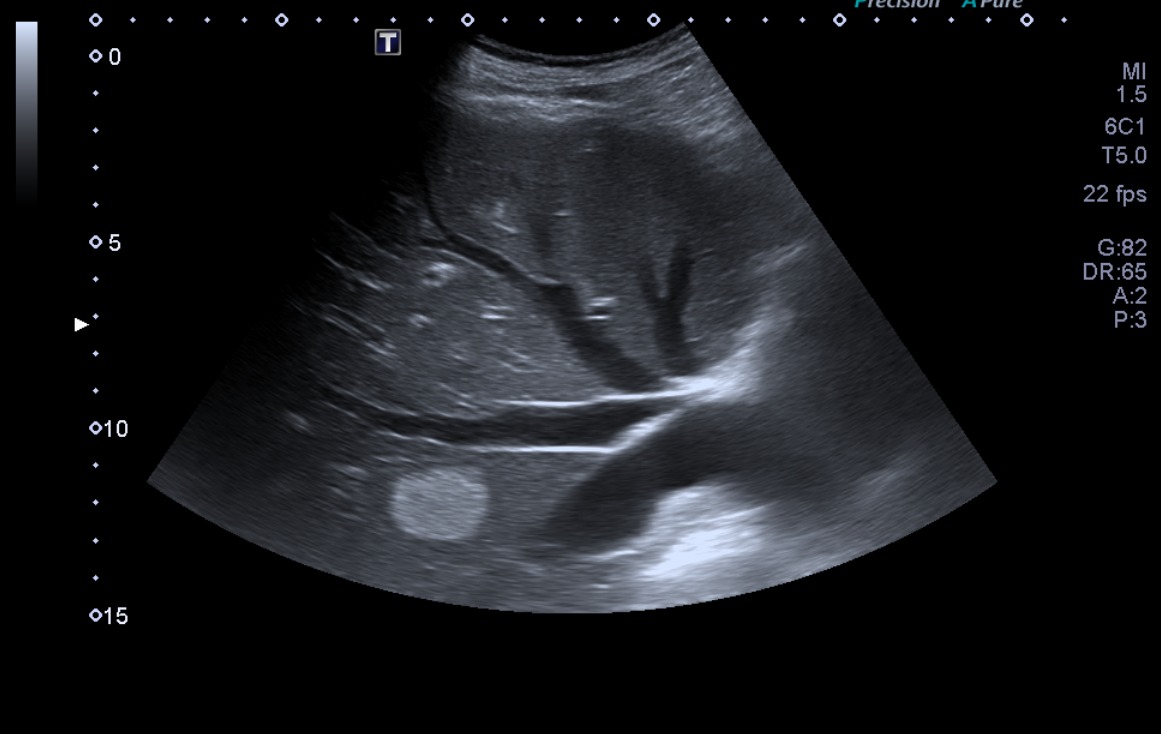

• Anamnesis y exploración: el paciente consultó hace un año por dolor en miembros inferiores, que se iniciaba con la deambulación y cedía con el reposo. Con exploración osteomuscular normal y sin palparse pulsos pedios, se solicitó ecografía para descartar aneurisma de aorta e iliacas. (Ecografía 1).

• Ecografía 1 (hace 1 año): segmento de aorta visible de 2 cm de diámetro, arterias ilíacas no accesibles. Leve ectasia de venas suprahepáticas y vena esplénica. Ligera dilatación de la vía biliar intrahepática. Hígado de morfología y ecogenicidad conservada, nódulo ecogénico bien delimitado en lóbulo derecho de 2,5 cm, compatible con hemangioma.